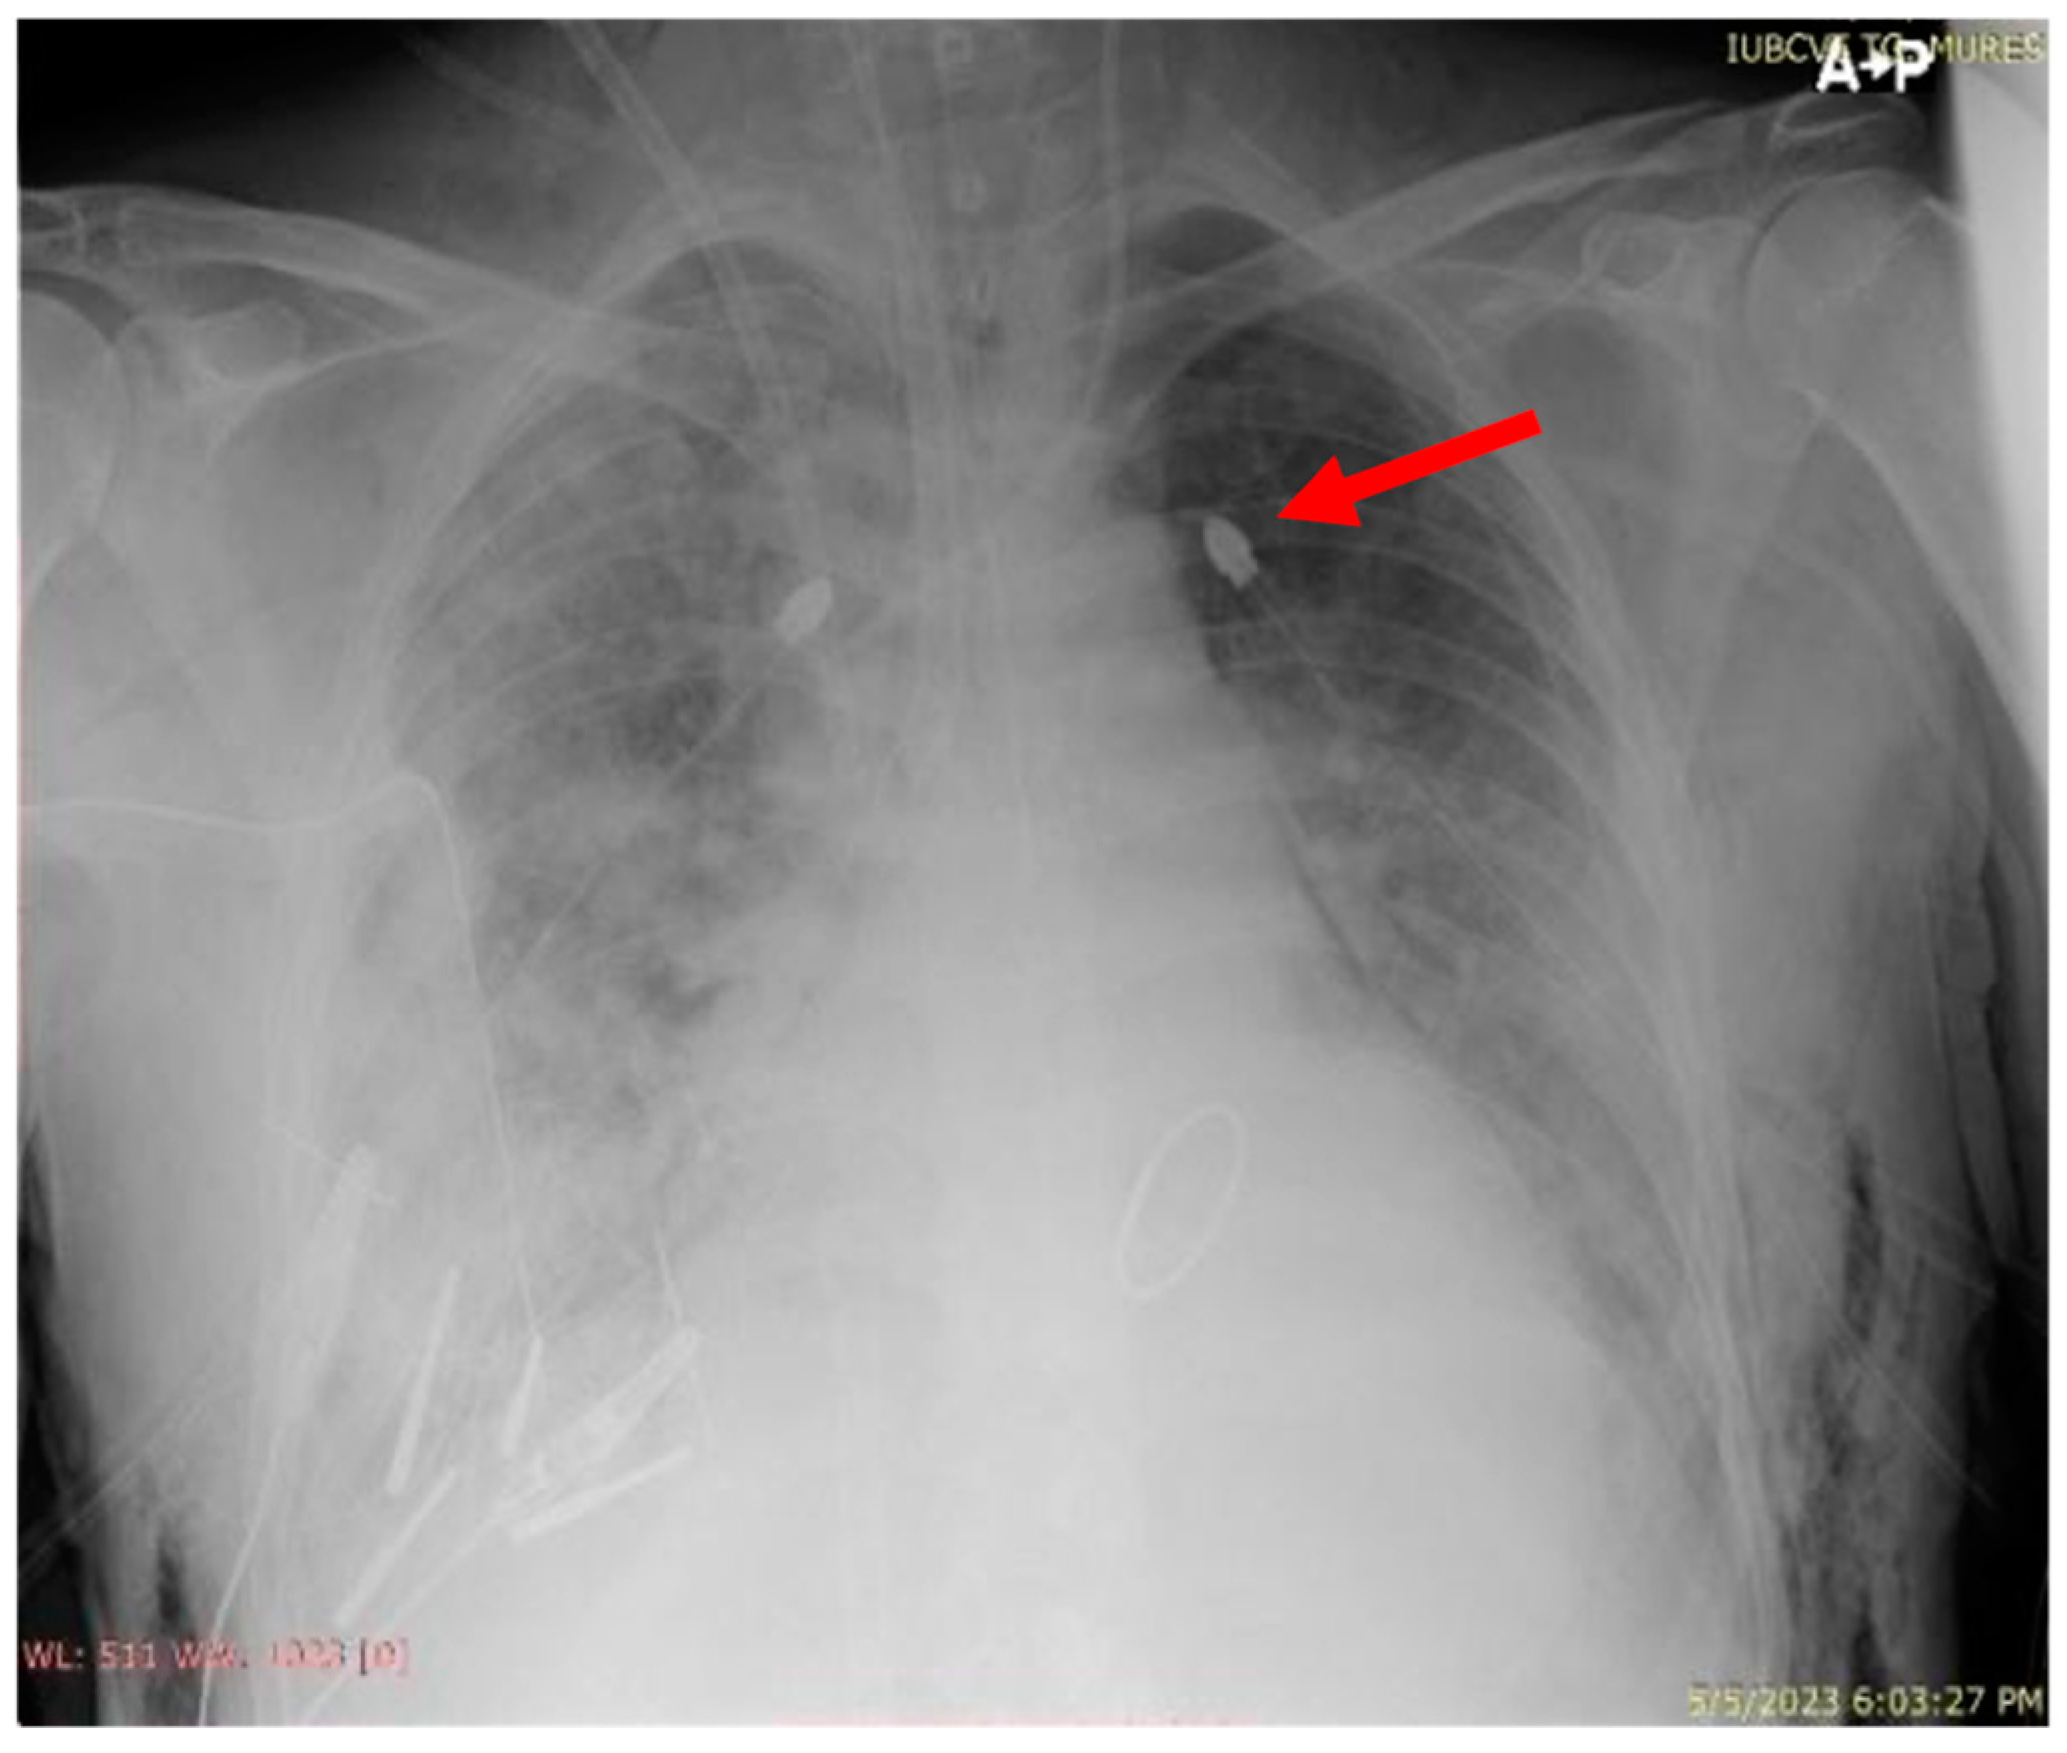

| Postoperative evolution | Right after Intensive Care Unit (ICU) admission, hypoxia abruptly developed, and serous discharge was aspirated through the endotracheal tube. The thoracic X-ray performed revealed dense alveolar opacities on the entire right hemithorax, confirming the diagnosis of unilateral pulmonary edema. | |

| Day 1 | The patient developed a left pneumothorax, confirmed by thoracic X-ray, worsening respiratory parameters, therefore requiring the insertion of a drainage tube. A thoracic X-ray after drainage confirmed the correct positioning of the tube and the complete expansion of the left lung. | |